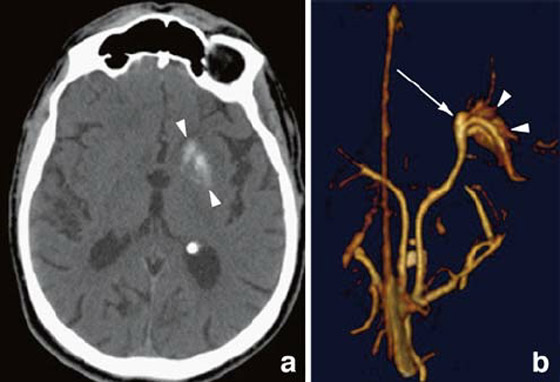

وأوضح الأطباء أن ما حدث كان بسبب تناول الرجل لحم الخنزير المقدد غير المطبوخ جيدًا، وفقا لما ذكرت شبكة بريطانية، حيث كشف تصوير بالأشعة المقطعية أجراه أطباء لدماغ الرجل، عن بيوض الدودة الشريطية، كما تم تشخيص المريض بداء الكيسات المذنَّبة العصبي.

يشار إلى أن هذا الداء يعدّ نوعاً خاصاً من داء الكيسات المذنبة، ويحدث بسبب عدوى بالشريطية الوحيدة، وهي شريطية حقيقية (Eucestoda) تُوجد في الخنازير، والتي يمكن أن تصل إلى الأنسجة مثل العضلات والدماغ. في حين نفى المريض تناول طعام نيء أو وجبات من الشارع، إلا أنه اعترف بعادة تناول لحم الخنزير المقدد المطبوخ بشكل خفيف وغير المقرمش معظم حياته. في حين أكد الباحثون أن الرجل تعرض للعدوى الذاتية، بعد عدم غسل اليدين بشكل لائق.